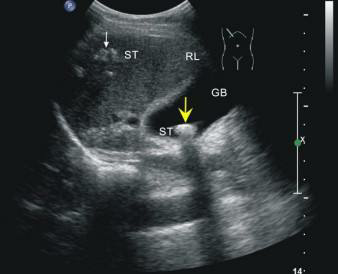

這位先生姓錢(qián),自訴飲酒后出現(xiàn)胸骨后疼痛4小時(shí),呈壓榨性,持續(xù)不緩解,伴大汗、面色蒼白、惡心、欲吐,既往無(wú)高血壓、糖尿病、冠心病病史,吸煙史30年,偶有飲酒,入院時(shí)查體血壓為120/80mmHg,心率:98次/分,節(jié)律規(guī)整,未聞及明顯雜音。心電圖:竇性心律,心率98次/分,II、III、aVF導(dǎo)聯(lián)病理性Q波,ST段下移,不正常心電圖。不除外急性心肌梗死。急檢心肌酶及超敏肌鈣蛋白、淀粉酶,結(jié)果回報(bào)心肌酶、超敏肌鈣蛋白無(wú)明顯改變。疼痛時(shí)復(fù)查心電圖較前無(wú)變。胸痛癥狀仍持續(xù)不緩解,給予曲馬多止痛不改善。請(qǐng)示李桂武主任醫(yī)師,主任給予詳細(xì)詢問(wèn)病史、癥狀及查體,患者膽囊區(qū)有壓痛無(wú)反跳痛,考慮患者可能存在膽囊性疾病,不排除腎結(jié)石,指示:急檢肝膽胰脾彩超及泌尿系彩超。我急忙陪著患者及家屬去門(mén)診彩超室做肝膽胰脾及泌尿系彩超。結(jié)果如下圖。提示膽囊結(jié)石。

請(qǐng)肝膽外科梁博主任會(huì)診后建議行CT檢查以進(jìn)一步明確診斷,肝膽胰脾CT結(jié)果可見(jiàn)膽囊不大,內(nèi)見(jiàn)高密度結(jié)節(jié),約10mm(IM33),膽總管無(wú)擴(kuò)張。建議轉(zhuǎn)入肝膽外科行手術(shù)治療。